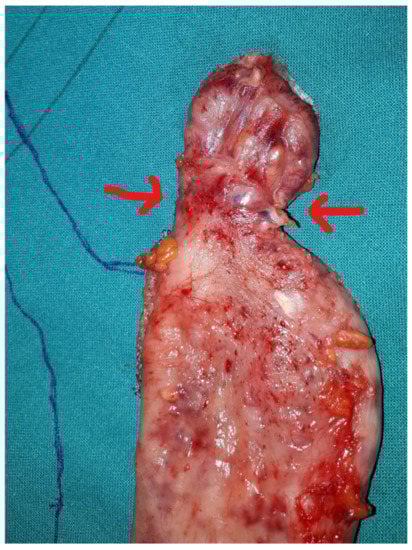

- Each reload of the stapler must be calibrated based on the thickness of the gastric wall, as well documented in the work of Elariny et al. [13], providing the right compression and hemostasis of the tissue.

- The staple line should stay at least 1 cm away from the esophago-gastric junction.